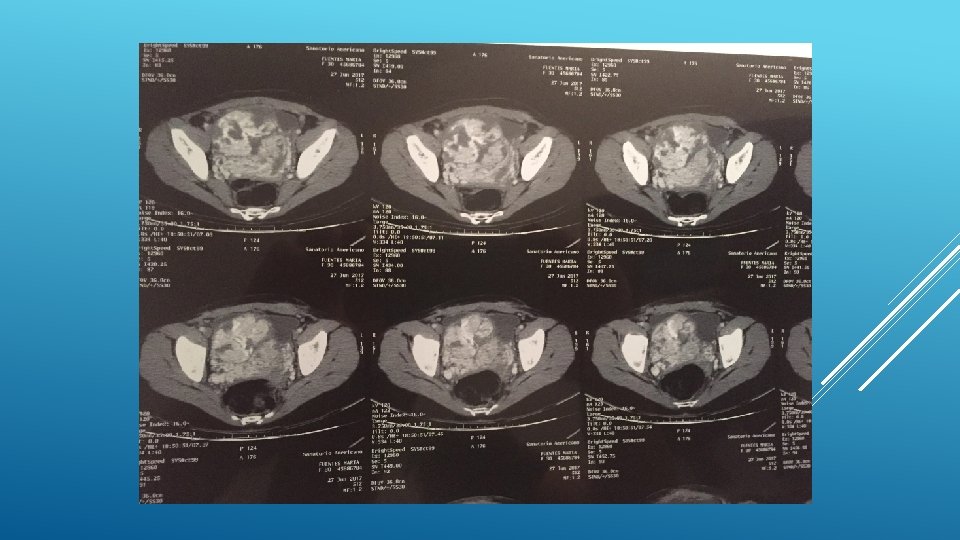

13/6/17 INGRESA A SANATORIO AMERICANO 30 SEMANAS EG, IMPRESIONA SIGNO ACOLCHONAMIENTO, METRORRGIA ACTIVA ESCASA. SIN REPERCION MATERNO FETAL. HEMOGRAMA: HEMOGLOBINA 13, 6 ECOGRAFIA INGRESO: 29 SEM, FULC, PFE 1420 gr, LA normal. PLACENTA OCLUSIVA TOTAL , PRESENTA UN SECTOR DEL ESPACIO RETROPLACENTARIO QUE IMPRESIONA NO CONSERVADO. SE VISUALIZAN LAGUNAS VASCULARES AL UTIILIZAR DOPPLER COLOR EN DICHO SECTOR. NO SE DESCARTA ACRETISMO PLACENTARIO. INGRESA A SALA CONDUCTA EXPECTANTE. 15/6 PERSISTENCIA DE METRORRAGIA ACTIVA, ASOCIANDO REPERCUCION HEMATOLOGICA (HB 9, 9) CON UN PROBABLE ACRETISMO PLACENTARIO SE DECIDE INTERUPCION DE LA GESTACION MEDIANTE OPERACIÓN CESÁREA.

CESÁREA: SE COSTATA PLACENTA PERCRETA EN ESPACIO VESICOUTERINO, HISTEROTOMIA SEGMENTARIA ALTA, SE EXTRAE FETO SM EN PODALICA VIGOROSO. SE COMPRUEBA PLACENTA PREVIA OCLUSIVA TOTAL QUE ATRAVIESA PARED UTERINA. SE LIGA CORDON Y SE DECIDE HISTERECTOMIA.

48 HS INGRESADA EN CTI, BUEN EVOLUCION INGRESA A SALA. BUENA EVOLUCION EN SALA, REQUIRIENDO TRANSFUCION DE GR, HIERRO IV Y EPO. SE REALIZO ATB PROFILACTICA Y SE COMIENZA TROMBOPROFILAXIS AL 6 TO DIA DEL PO. ECOGRAFIA 20/6 NORMAL. SE OTORGA ALTA 26/6 27/6 REINGRESA POR CUDRO SINCOPAL. SE DESCARTO TEP MEDIANTE ETT Y ANGIOTAC: PELVIS EN LECHO QUIRURGICO , COLECCIÓN HETEROGENEA CON IMPORTANTES AREAS DE SANGRADO ACTIVO DE APROX 101 X 100 X 90. LA MISMA COMPRIME VEJIGA.

TAC 16/8 A NIVEL PELVIANO SUPERIOR Y POSTERIOR A VEJIGA COLECCIÓN HIPODENSA, DENSIDAD SIMILAR AL LIQUIDO, PRESENTA BURBUJAS AEREAS EN SU INTERIOR. MIDE APROX 86 x 87 x 63 mm. VEJIGA CONTORNOS REGULARES Y DENSIDAD HOMOGENEA, FONDO DE SACO DE DOUGLAS LIBRE. NO SE OBSERVAN ADENOMEGALIAS PELVICAS. CONTINUA EN CONTROL AMBULATORIO CON ONCOLOGIA Y GINECOLGIA.